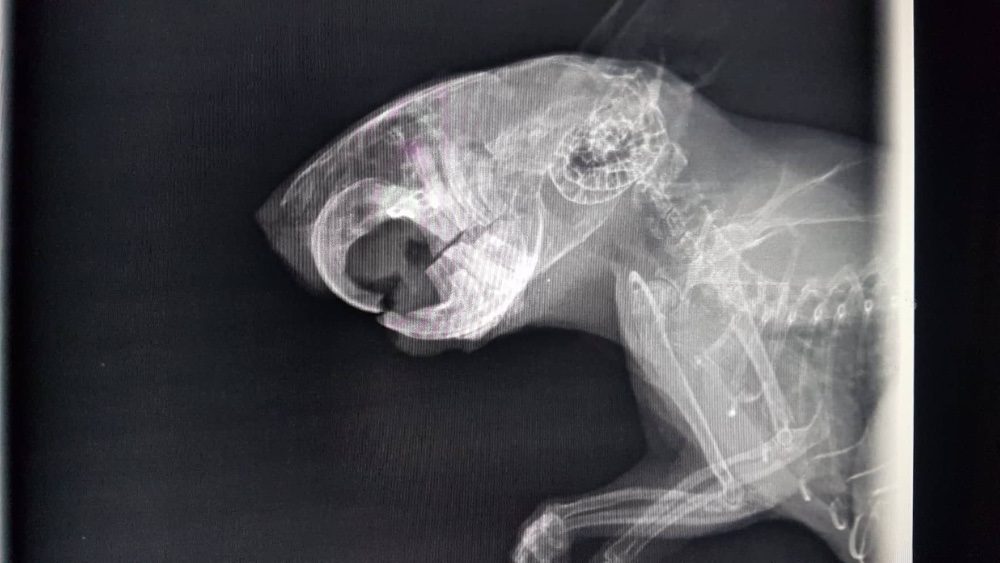

Also ab zum Tierarzt. Sie hat keine Veränderungen feststellen können - auch im Röntgenbild nicht. Er hat aber gefressen, nur eben langsam und eher die weichen Sachen. Nach ein paar Tagen wurden dann auch die unteren Schneidezähne schwarz

Und dann... tja, dann sind irgendwie alle Zähne nacheinander abgebrochen und sind in wunderschönem, gelblichen, gesunden Farbton wieder gekommen. Okay... ich verstehe es nicht, bin aber erstmal zufrieden. Trotzdem isst der blinde Zauberer nur mäßig festes Futter, schlingt aber den Brei. Also wieder mal zum Doc, wieder die Zähne gemacht, ein paar Spitzen geschliffen, aber sonst hat er gute Zähne. Auch das Röntgenbild scheint das zu bestätigen.

Und wenn ich mir sein letztes Röntgenbild so ansehe... irgendwie (jetzt wo man es weiß) sieht es schon da irgendwie anders aus, als hier

- merlin_roentgen.jpg (136.79 KiB) 2392 mal betrachtet